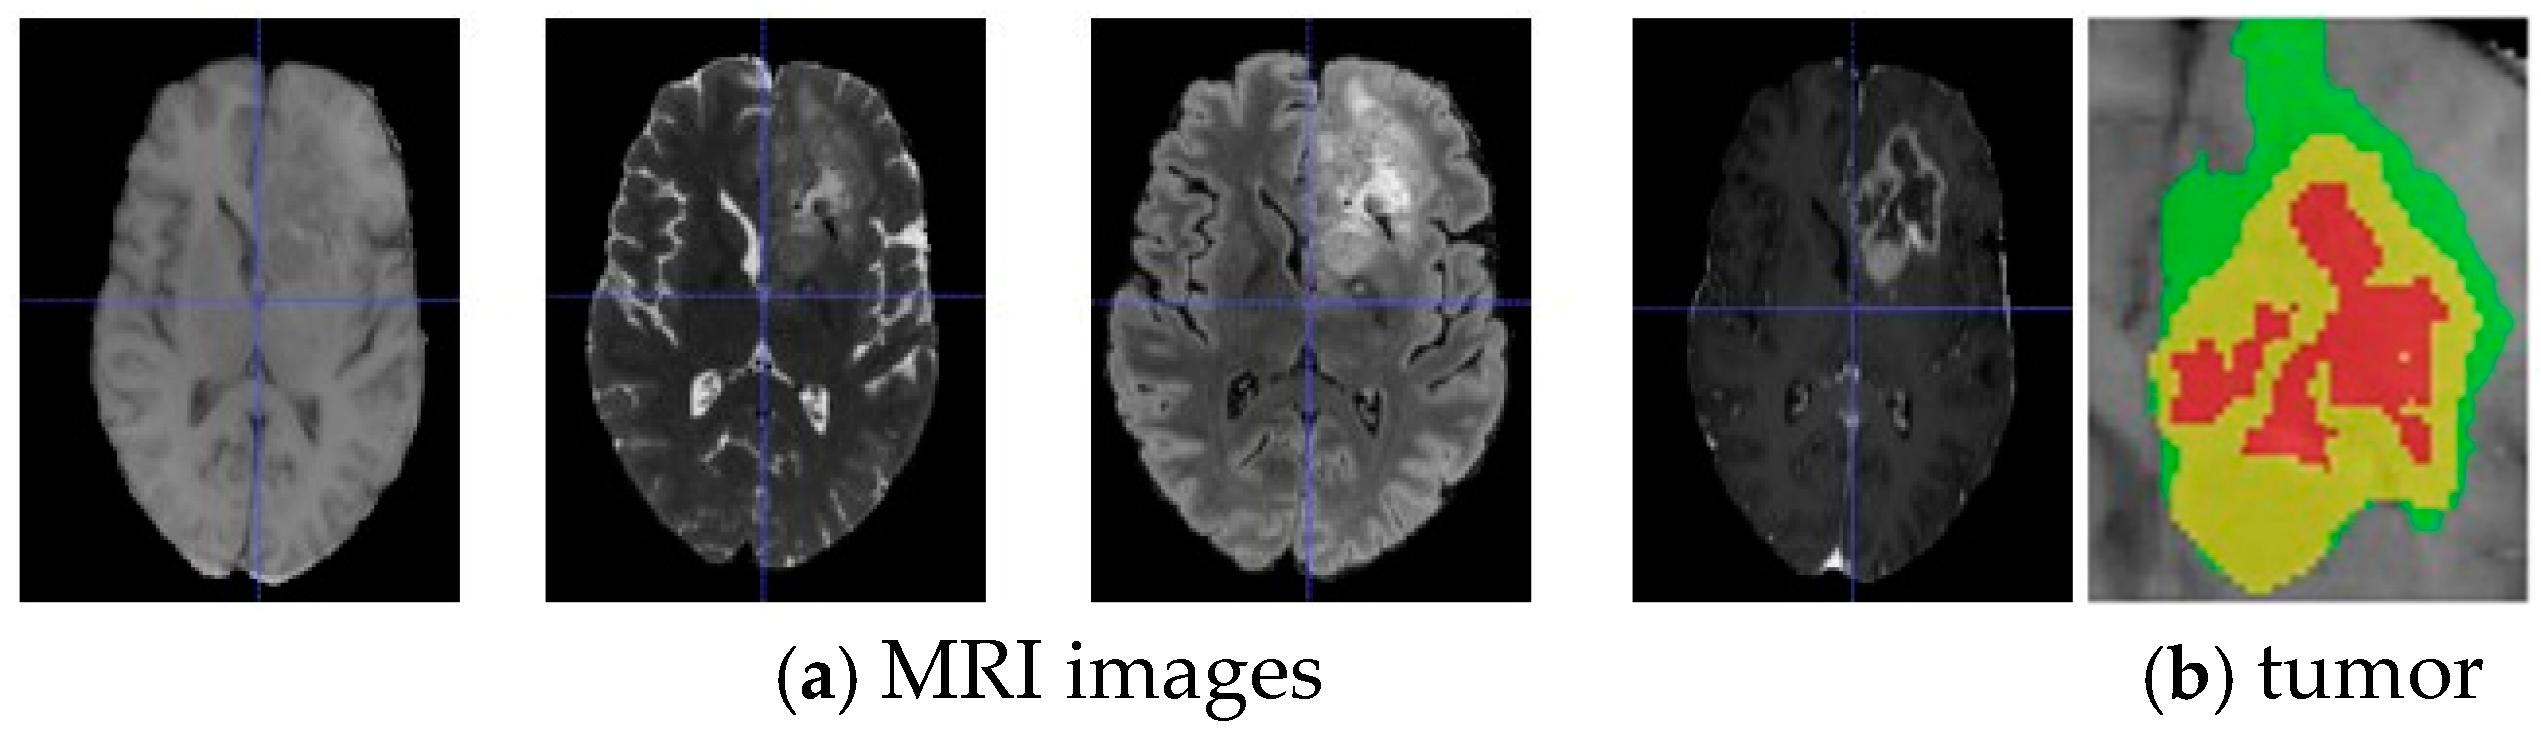

3.1. Dataset and Pre-Processing